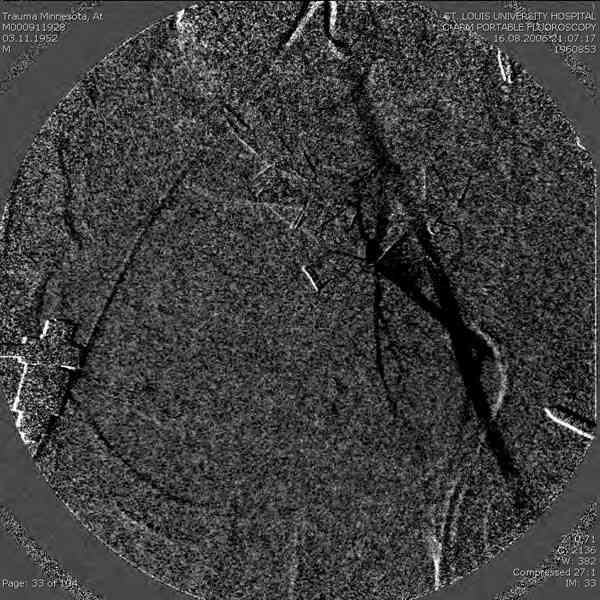

Имелся стойкий болевой синдром, неопороспособность левой н/конечности, моторные и сенсорные нарушения в левой голени и стопе, патологическая подвижность левой половины таза. Первым этапом закрыто в аппарате исправили деформацию ( в течении 2,5 нед). Вторым закрытое введение илиосакральных винтов в крестец (канюллированные 7,2 мм Chm) + туннелизация зоны псевдоартроза спицама Киршнера, реконструкция передних отделов таза, накостный остеосинтез . Аппарат частично демонтирпован, оставлена "передняя рама" После устранения деформации отмечен регресс неврологической симптоматики, уменьшение болевого синдрома. Интересующие вопросы: 1. Прогноз для сращения псевдоартроза крестца. 2. сроки нагрузки весом левой половины таза. Буду очень признателен за ваши мнения по этому поводу.A female 32 y.o. admitted to our unit 9 months after initial injury with pain, inability to bear weight at the left lower limb, sensor and motor disturbances in the left foot and tibia, with mobility of the left hemipelvis.At first closed reduction was performed by an external fixator within 2,5 weeks. After correction her pain decreased and some neurological progress was achieved. Now two iliosacral screws 7,2 mm were inserted, and anterior lesion was fixed by a plate. External fixator was partially unmounted, only anterior frame left in place.Images attached.How would you evaluate chances of healing of the sacrum with the current position?When would you allow weight-bearing of the left leg?THX in advance.

Примерно такой фиксатор наложил вчера ночью, но патология была экстренная травма: больному 53 года, поступил после мотоциклетной травмы, черепно-мозговой, абдоминальной, челюстно лицевой с потерей одного глаза, сосудистой и из скелета перелом крестца слева с диастазом симфиза и множественные переломы ребер.

Здесь соблюдался алгоритм больному с внутритазовым кроветечением после нестабильного перелома таза.

Обычно поступившим в приемное отделение больным с переломами конечностей, полученным в результате автоаварии или результате других скоростных травм по протоколу проводятся исследования на КТ ургентно. Череп всем бессознательным больным и живот при подозрении на внутреннее кровотечение.

Шоковым с повреждением таза, перед КТ исследованем накладывается антишоковые трусы.

Для стабилизации перелома и кровопотери, сперва была попытка наложения простыни вокруг таза для уменшения объема таза. Для оперативного доступа в области живота и передней части таза простыню заменили на Beam Bag (матрац который после удалении воздуха принимает контуры тела).

Одновременно с хирургами, которые занялись ксплоративной лапаротомией, мы приступили к фиксации временным аппаратом для уменьшения диастаза симфиза. После установки аппарата удалось стабилизировать давление, потом наше место занял сосудистый хирург, который нашел кровоточащую левую артерию epigastrica. Кровоточаший сосуд затромбизировал эндоваскулярно введением 4 coil placement.

Много кровепотери было из лицевых ран. Кроме забрюшинной гематомы, крови накопилось в абдоминальной части между мышечными стенками и под кожей. Кровопотерю заместили более 20 доз препаратов крови и INR опустился изначалнего 9.5 до 1.0 в конце. Находится в реанимации, стабильный, надеемся через несколько дней займемся окончательной фиксацией переломов костей таза.